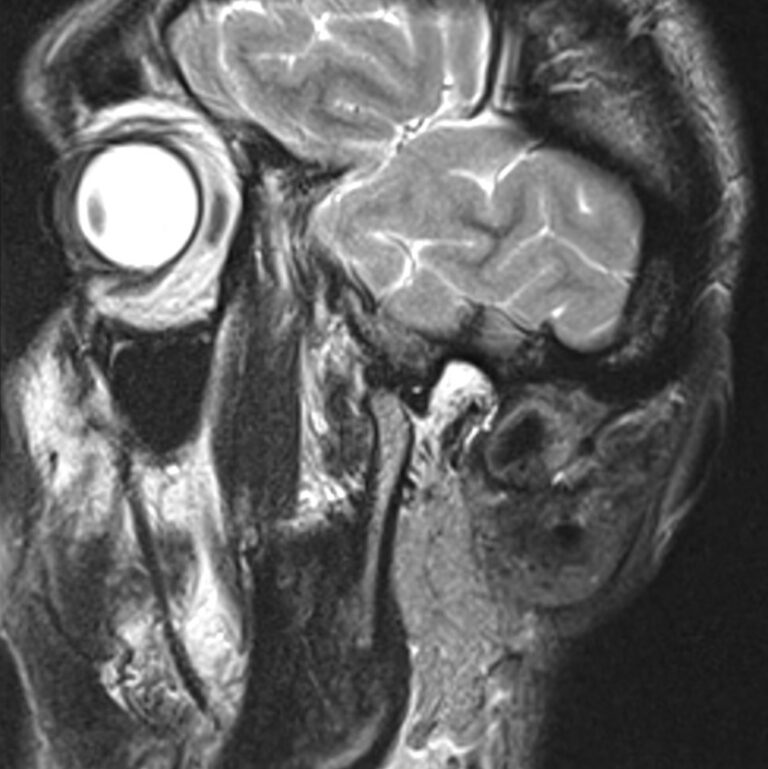

Височно-нижнечелюстной сустав является парным комбинированным суставом и имеет сложное строение. В него входят суставные ямки височной кости, суставные головки нижней челюсти и расположенные между ними хрящевые пластинки – мениски, выполняющие роль амортизаторов.

Чаще всего дисфункция височно-нижнечелюстного сустава обусловлена внутренним повреждением, смещением мениска и суставной головки нижней челюсти. Для определения степени смещения внутрисуставных структур выполняется функциональная проба с проведением МРТ в двух положениях:

• с закрытым ртом;

• с открытым ртом.

Магнитно-резонансная томография является наиболее точным и эффективным методом диагностики поражения височно-нижнечелюстных суставов, так как позволяет получить детальную информацию о состоянии не только костей, но и связочного аппарата, хрящей, менисков, жевательных мышц, окружающих мягких тканей.

При проведении магнитно-резонансной томографии на изображениях визуализируются: височная кость, головка мыщелкового отростка нижней челюсти, суставная щель. Помимо костных структур МРТ позволяет оценить состояние мягких тканей – внутрисуставного диска и связочного аппарата височно-нижнечелюстного сустава, жевательных мышц.

МРТ ВНЧС с капой включает в себя два протокола: с открытым ртом и с закрытым ртом. Данная функциональная проба позволяет проследить степень смещения внутрисуставных анатомических структур и оценить биомеханику движений в суставе.

Протокол МРТ ВНЧС предусматривает проведение исследования в двух положениях: с открытым ртом и закрытым ртом. Данная функциональная проба дает возможность оценить биомеханику работы височно-нижнечелюстного сустава.